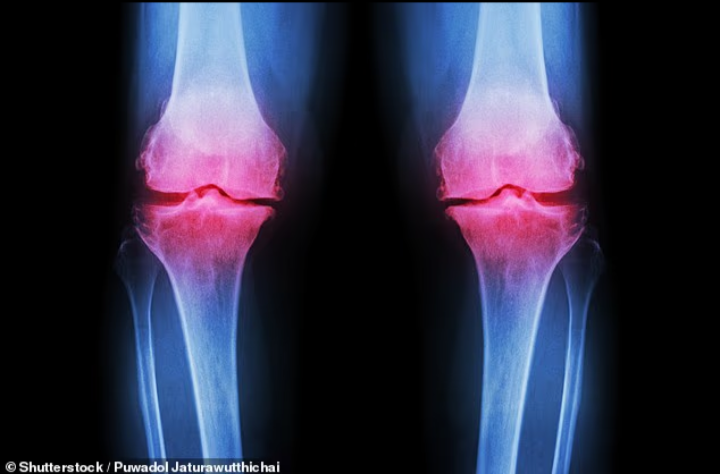

كشفت دراسة علمية حديثة أن مكملًا غذائيًا بسيطًا ورخيص الثمن قد يساعد في تقليل آلام خشونة المفاصل، خاصة آلام الركبة التي يعاني منها ملايين الأشخاص حول العالم.

مكمل غذائي رخيص قد يخفف آلام خشونة الركبة

وشملت الدراسة 117 شخصًا بالغًا يعانون من خشونة الركبة، وتم تقسيمهم إلى مجموعات حصلت على:

وتمت متابعة المشاركين لمدة 6 أسابيع مع تقييم مستوى الألم والقدرة الحركية.